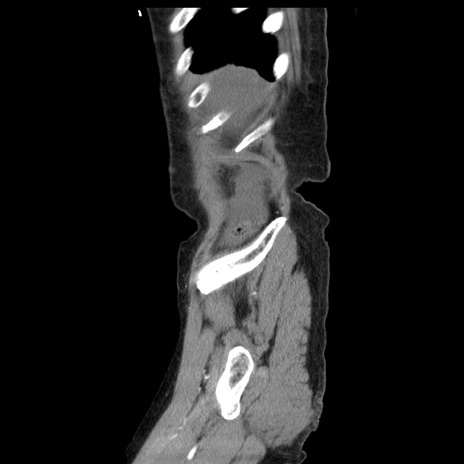

症例1(矢状断像)

【症例】80歳代女性

【主訴】腹痛

【現病歴】8時間前から腹痛あり来院。

【既往歴】糖尿病、脂質異常症、子宮体癌にて子宮全摘術

【身体所見】意識清明・会話良好だが腹痛で苦悶様、全腹部にわたって反跳痛と圧痛あり

【データ】WBC 13600、CRP 0.14、LDH 224、CK 90